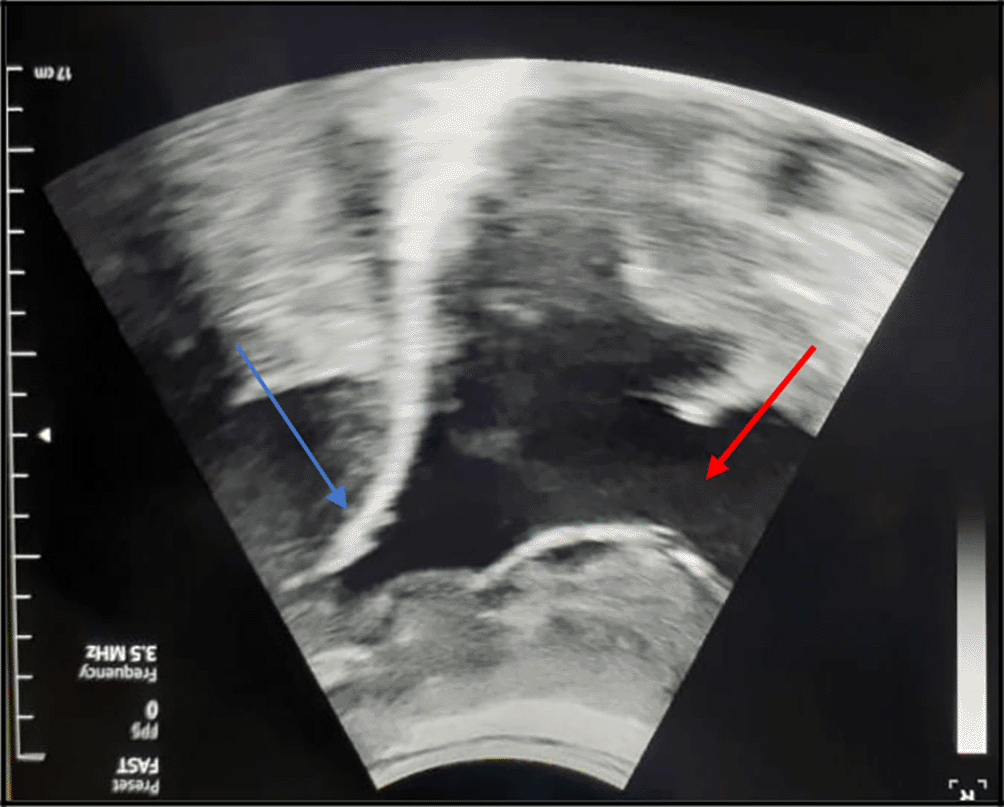

The chest X-ray showed a left-sided pleural opacity with signs of compression (Figure 1). So, an exploratory and evacuating ultrasound-guided pleural puncture was immediately performed. The thoracic ultrasound revealed a massive anechoic, free left pleural effusion associated with many pleural nodules (Figure 2). Therefore, a malignant origin was suspected. Analysis of the pleural fluid showed a serohaematic exudative fluid, with a predominantly lymphocyte formula (80%). A Gram stain fast bacilli (AFB) stain and cultures for (bacterial and tuberculosis) were all negative. Besides, we did not find any malignant cell in the pleural puncture cytology.

The diagnosis was very challenging in our patient. In fact, we initially suspected an advanced stage lung carcinoma giving the chest CT scan’s findings, or a mesothelioma because of the multinodular aspect of the pleura in the chest ultrasound and “the grape-cluster” appearance as seen in thoracoscopy. The histological exam of the pleural guided biopsy helped us to assess the right diagnosis.